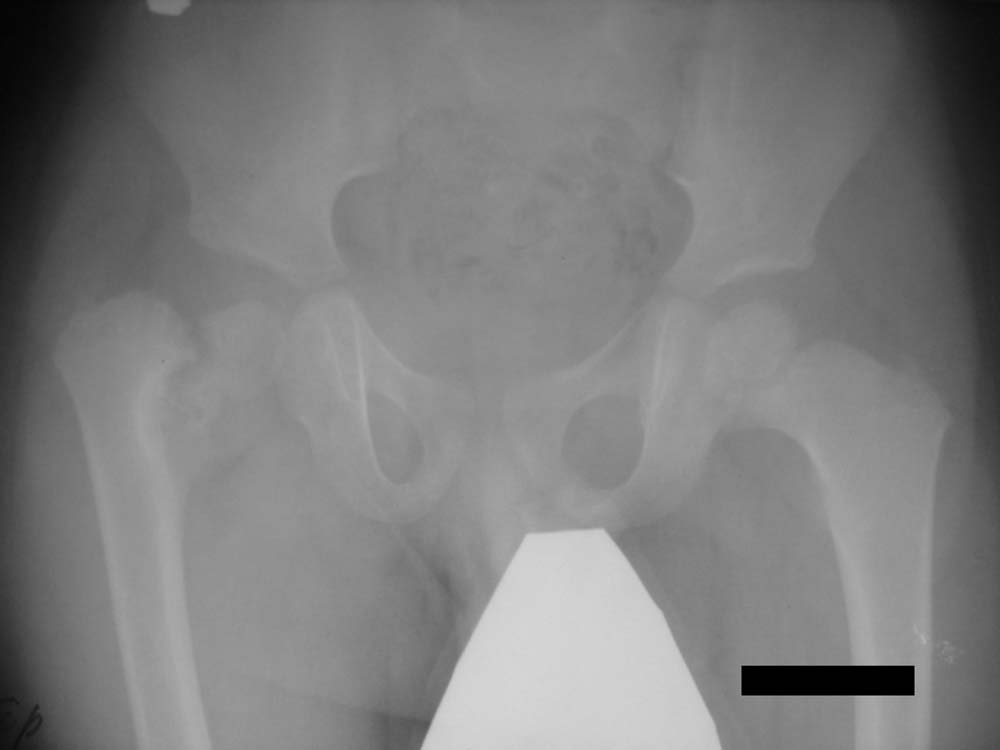

В представленном случае, по всей видимости, имеет место застарелый перелом со смещением отломков, в результате чего и произошло уменьшение шеечно-диафизарного угла.

В данном случае, по всей видимости, генез травматический, но возникает некоторое недоумение тот факт, что в понятие «детской дистрофической coxa vara» включены патологические состояния врожденного, травматического рахитического, эндокринного и т.д. генеза.

Нет, травмы в данном случае не было. Имеет место дистрофическая coxa vara, вероятнее всего, врождённаяю. Эпифизеолиз головки, который мы видим на снимке, как мы считаем, наступил вследствие нарушений биомеханики в суставе - ШДУ практически 90 градусов. Добавлю, что факт травмы родители категорически отрицают. Ребёнок постепенно начал хромать, хромата усиливалась на протяжении 6 месяцев.